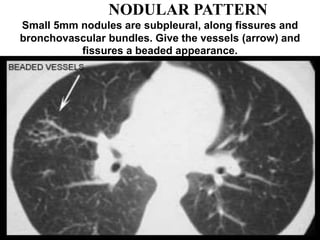

NODULAR PATTERN

Small 5mm nodules are subpleural, along fissures and

bronchovascular bundles. Give the vessels (arrow) and

fissures a beaded appearance.

Nodular thickening of the

peri-broncho-vascular interstitium